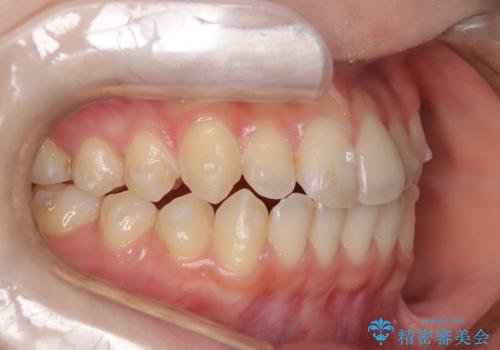

前歯のガタつき、下顎の前突感を治したい インビザライン矯正例

- 治療計画

- 学生時代に矯正治療を経験されていましたが、その後の後戻りによる前歯の叢生・下顎の前突感を主訴に来院されました。叢生や口元の突出感が軽度であった為、非抜歯にて側方拡大やIPRを組み込んでインビザラインにて治療を計画しました。前歯部にクロスバイトがあり、治療途中に上顎前歯が下顎前歯を乗り越えなければならない時期もありましたが、患者様の協力的なマウスピース装着もあり、良好な配列を達成しました。上下左右の親知らずは、当院にて矯正開始前に抜歯しました。